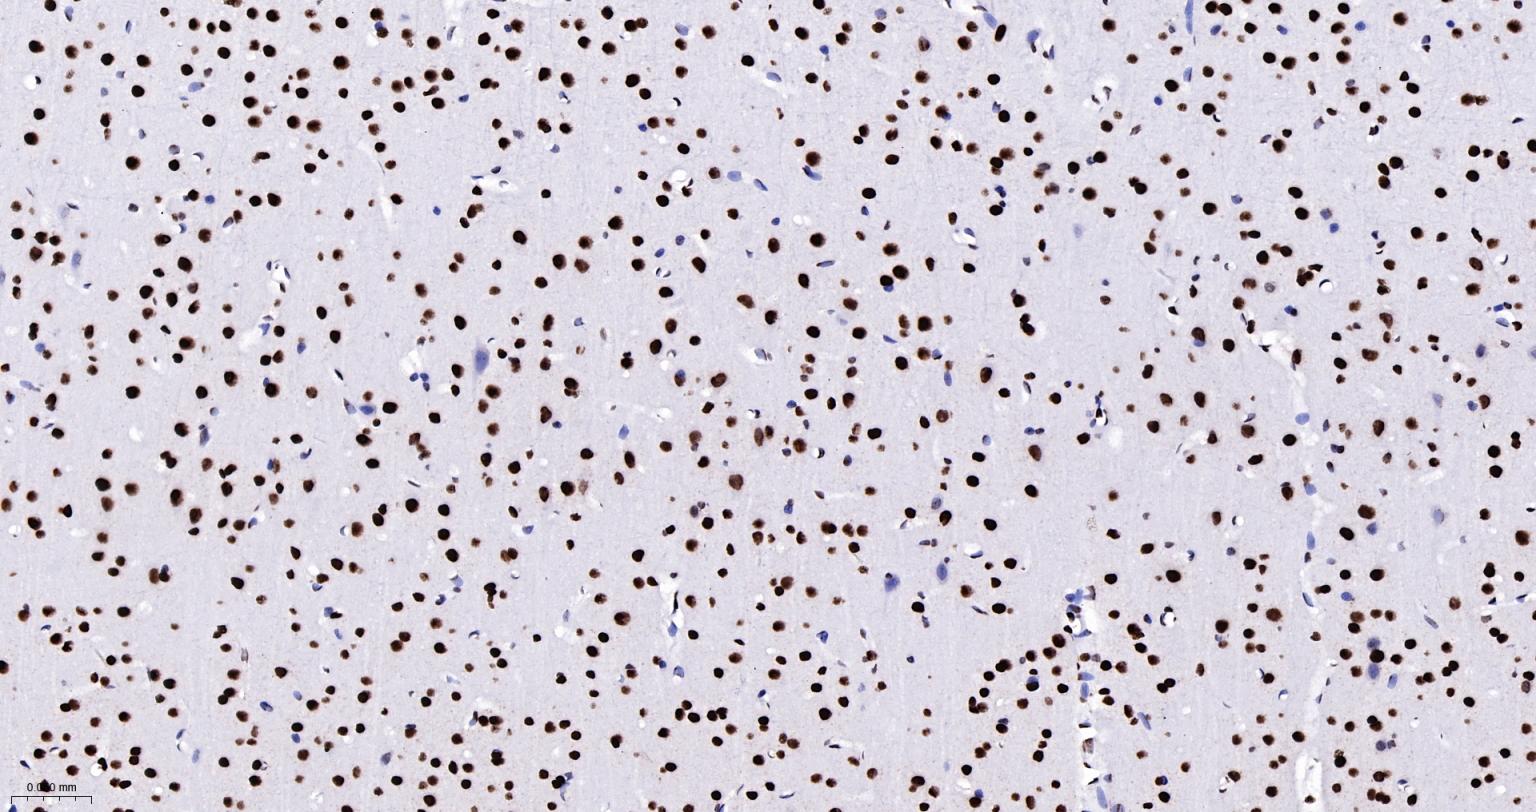

Paraformaldehyde-fixed, paraffin embedded Rat Cerebrum; Antigen retrieval by boiling in sodium citrate buffer (pH6.0) for 15 min; The section was incubated with SFPQ Monoclonal Antibody, Unconjugated (bsm-61746R) at 1:200 overnight at 4°C, followed by conjugation to the bs-0295G-HRP and DAB (C-0010) staining.